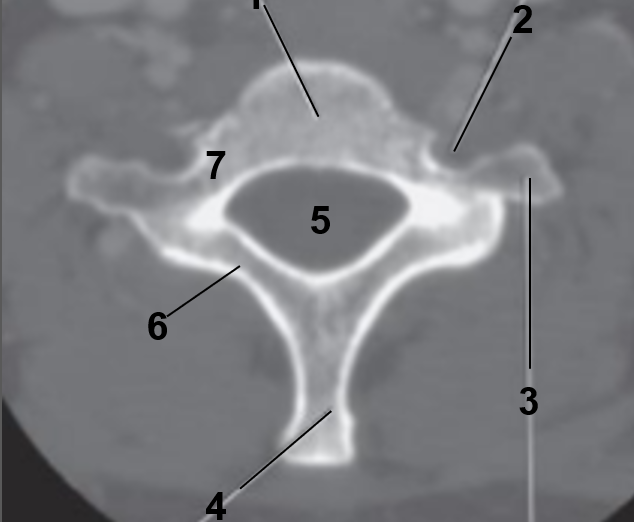

1

Transverse foramen

2

Anterior arch

3

Transverse Process

4

Posterior arch

5

Superior articular facet

6

Dens

7

Vertebral Foramen